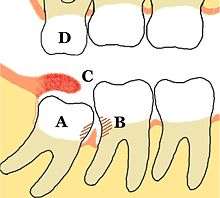

Some problems which may or may not occur with third molars: A Mesio-impacted, partially erupted mandibular third molar, B Dental caries and periodontal defects associated with both the third and second molars, caused by food packing and poor access to oral hygiene methods, C Inflamed operculum covering partially erupted lower third molar, with accumulation of food debris and bacteria underneath, D The upper third molar has over-erupted due to lack of opposing tooth contact, and may start to traumatically occlude into the operculum over the lower third molar. Unopposed teeth are usually sharp because they have not been blunted by another tooth.